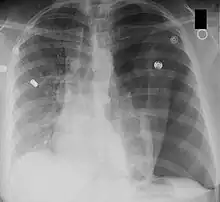

Left tension pneumothorax seen as a large, well-demarcated area devoid of lung markings with tracheal deviation and movement of the heart away from the affected side (mediastinal shift). There is also small pleural effusion on the left side.

Mediastinal shift is the deviation of the mediastinal structures towards one side of the chest cavity, usually seen on chest radiograph. It indicates a severe asymmetry of intrathoracic pressures.[1] Mediastinal shift may be caused by volume expansion on one side of the thorax, volume loss on one side of the thorax, mediastinal masses and vertebral or chest wall abnormalities. An emergent condition classically presenting with mediastinal shift is tension pneumothorax. It is also a useful indicator of malignant pleural effusion.[2]